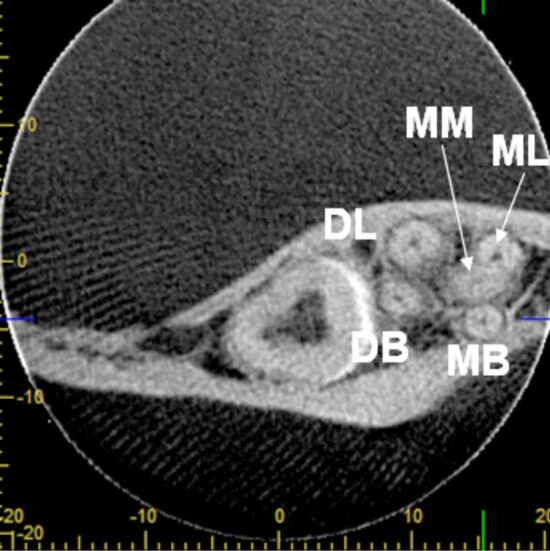

特别是在磨牙中,有时可能有异常的额外根管,个别病例中牙齿内部形态的复杂性有时与公认的分类规则不匹配,并突出了在牙髓治疗过程中错过解剖结构的风险。据我们所知,一个永久性下颌第二磨牙有五个独立的根,三个近中根和两个远端根,每个根都有一个根管,目前尚未报道。尽管治疗困难,但通过使用牙科手术显微镜和小视场的锥束计算机断层扫描(CBCT),可以成功地接近这颗牙齿。虽然CBCT不是一种常规的影像学检查,但在非典型牙齿解剖的情况下,旨在制定适当的诊断和治疗计划,成功的临床结果优于照射剂量。

Especially in molars that may have sometimes aberrant additional root canals, the complexity of tooth internal morphology in individual cases sometimes does not match to admitted classification rules and underlines the risk of missed anatomy during the endodontic management. To our knowledge, a permanent mandibular second molar with independent five roots, three mesial and two distal, each of them harboring a single canal, was not yet reported. Despite the treatment difficulties this tooth could be successfully approached by using dental operative microscope and cone-beam computed tomography (CBCT) with small field of view. Though CBCT is not a routine imagistic examination, in case of atypical tooth anatomy aiming to establish adequate diagnosis and treatment plan, the successful clinical outcome prevails over the irradiation dose.